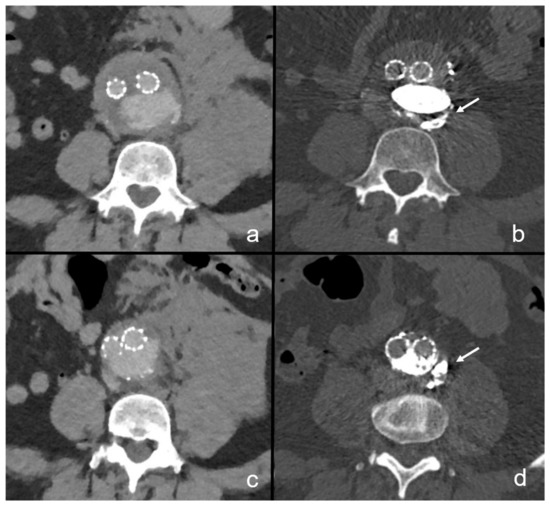

3.2. Case Descriptions

3.4. Imaging Follow-Up Results